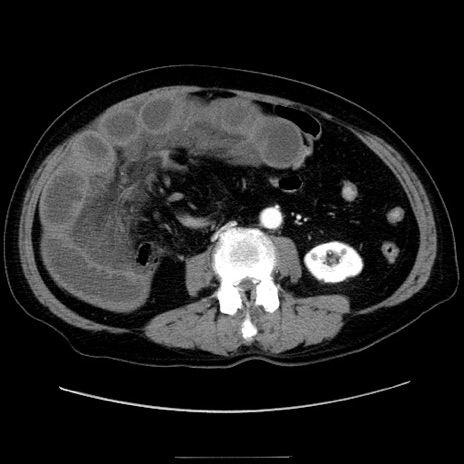

症例30(横断像)

【症例】80歳代男性

【主訴】臍周囲痛

【現病歴】約6時間前から臍下部痛が出現。次第に腹部膨隆・背部痛も生じてきたため来院。背部痛の場所は変化しない。

【既往歴】腎盂腎炎

【身体所見】意識清明、BT 36.3℃、BP  131/87mmHg、P 87bpm、SpO2 100%(RA)、臍周囲自発痛・圧痛あり、反跳痛なし、自発痛部位に一致して板状硬あり、腹部膨隆、腸雑音減弱、CVA tenderness両側陰性。

【データ】WBC 19600、CRP 0.33